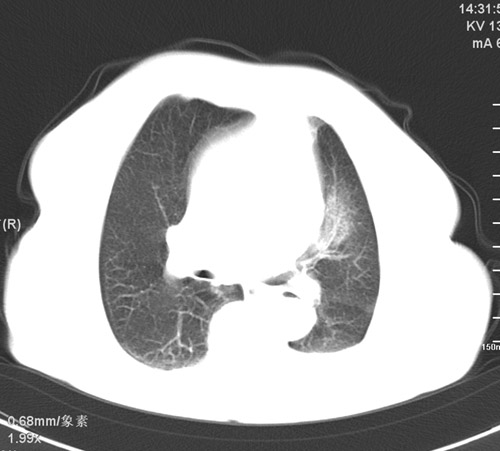

以下是引用杀毒软件在2009-4-22 18:45:00的发言:[br]考虑----左肺感染性病变〔真菌可能性大〕-----建议痰检。